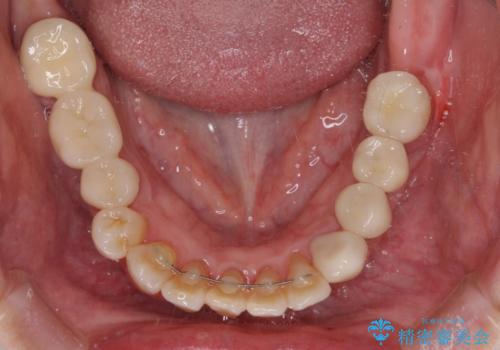

数多くの外科処置を行ったため、治療期間は長期間となりました。

一方、外科処置をしっかりと行ったことで、歯周病の状態は改善され、安定した状態にしあげることができました。